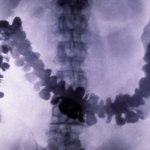

BCG

One of the dangerous diseases that, unfortunately, is still widespread in Russia is tuberculosis. BCG is designed to protect against it. Vaccination is carried out directly in the maternity hospital, unless, of course, there are contraindications. In the latter case, it is postponed, but then it can be given to the newborn after discharge from the maternity hospital in the children's clinic. No other BCG vaccinations are given on the day of vaccination, as it is quite difficult to tolerate. BCG is also given to premature babies, but with a smaller amount of antigen.

Usually this vaccination is placed in the left shoulder, which should not be wetted, scratched, etc. An abscess may appear in this place, but under no circumstances should it be squeezed out. Often a scar remains on the left shoulder for the rest of your life.

It is necessary to distinguish BCG from Mantoux. BCG is a vaccination that protects against the disease, and Mantoux is a procedure that checks whether a child has immunity from tuberculosis and is placed on the wrist. The first time it is performed after the child is one year old, and then Mantoux is performed quite regularly. If Mantoux reveals a lack of immunity, then BCG is repeated.

- Tuberculosis vaccine . Contains weakened bovine tuberculosis bacteria. They do not cause disease in humans. but lead to the formation of stable immunity. To develop stable immunity, the tuberculosis bacillus must be in the body constantly.